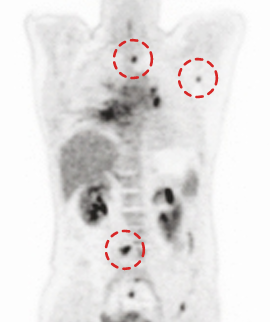

CASE #3

15 min (50%) Scan Without Denoising

15 min (50%) Scan With Denoising

30 min (100%) Scan Standard